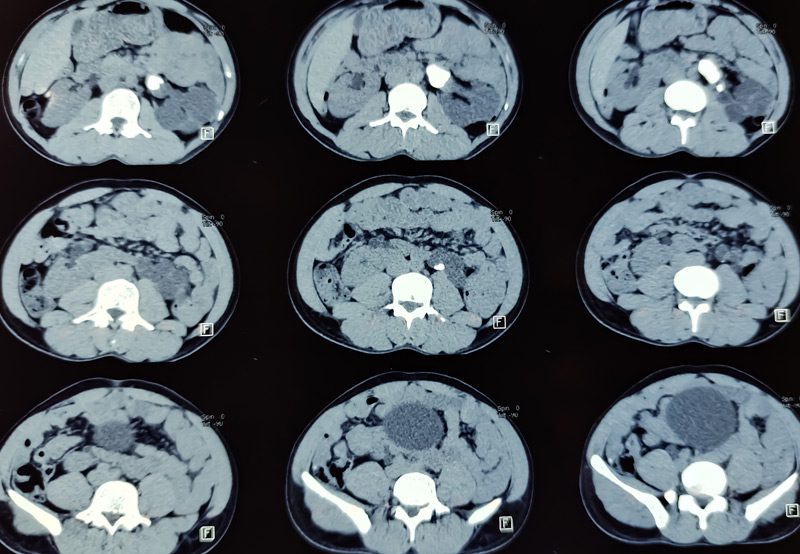

- CT Urogram or MRI: To identify the exact location and cause of the obstruction